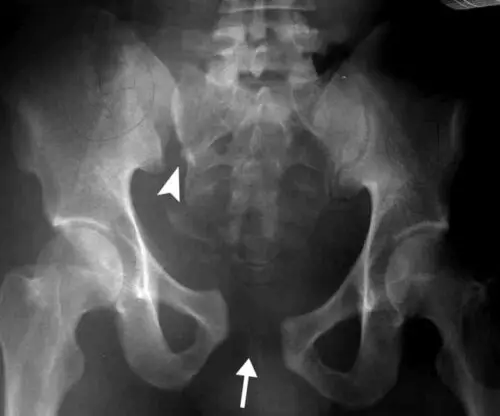

يتم تشخيص الكسر عادة باستخدام تصوير الأشعة السينية للحوض لتحديد تفاصيل الكسر بدقة، يطلب من الطبيب إجراء فحص بالأشعة المقطعية، حيث يجري الدكتور عمرو أمل أفضل دكتور عظام في مصر تقييم شامل للأعضاء الداخلية والأوعية الدموية والأعصاب المحيطة للتأكد من عدم وجود إصابات إضافية مرتبطة بالكسر.

ينتج عن كسر في مفصل الحوض ألم شديد يمنع المريض من تحريك مفصل الورك بشكل طبيعي، في حالات الكسر الحاد تترافق الإصابة مع تلف في أحد الأعضاء الداخلية أو تمزق في الأوعية الدموية، مما يؤدي إلى نزيف داخلي قد يقلل من تدفق الدم في الجسم.